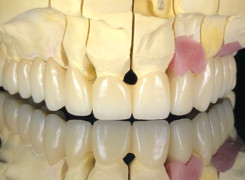

Pan Ryszard trafił do Naszego Gabinetu z jasno sprecyzowanym oczekiwaniem. Miał 84 lata i chciał odzyskać możliwość swobodnego spożywania posiłków oraz poprawienia sobie komfortu życia a także prosił aby przywrócić mu piękny uśmiech jakim cieszył się przed laty. Już na początku pierwszej rozmowy zastrzegł, że interesuje go wyłączenie rozwiązanie uzupełnieniem protetycznym stałym. Nie miał zamiaru użytkować żadnych protez ruchomych. Mając na uwadze powyższe wykonaliśmy Panu Ryszardowi zdjęcie pantomograficzne oraz badanie tomograficzne szczęki i żuchwy na postawie których zapanowywaliśmy Pacjentowi optymalne rozwiązanie – stałe uzupełnienie protetyczne w postaci 28 koron cyrkonowych zamontowanych do dwóch belek cyrkonowych które będą przymocowane do 16 implantów w konfiguracji 8 wszczepów w szczęcie 8 w żuchwie. Po omówieniu powyższego planu przystąpiliśmy do Wspólnej pracy której efekty w poszczególnych etapach prezentujemy poniżej.